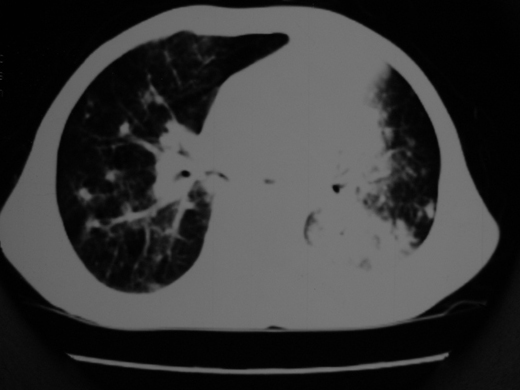

男69岁,年前胸片示肺感染治疗近一月今复查无明显好转,血象正常

双肺内不规则斑点状 片状及结节密实影,部分灶周见索条样影及\"树芽征\",左肺上叶实变,内见充气支气管影及斑状钙化,左侧少量胸腔积液,考虑1)双肺结核2)左侧胸腔积液

右肺多发片絮状结节状及时条索状影,左上肺实变,内可见虫蚀样空洞及支气管气象,左下肺片状及球形病灶,及胸腔积液征象,双肺病灶内多发钙化影,结合病史,考虑双肺继发型肺结核,左胸腔积液

右肺多发片絮状结节状及时条索状影,左上肺实变,内可见虫蚀样空洞及支气管气象,左下肺片状及球形病灶,及胸腔积液征象,双肺病灶内多发钙化影,上纵隔向左侧移位,结合病史,考虑双肺继发型肺结核,左胸腔积液。

右肺多发片絮状、结节状及条索状影,左上肺实变,内可见虫蚀样空洞及支气管气象,左下肺片状及球形病灶,有胸腔积液征象,双肺病灶内多发钙化影,上纵隔向左侧移位,结合病史,考虑双肺继发型肺结核,左胸腔积液。 建议结合ppd检查或纤支镜检查!

右肺可见大片状、云絮状改变。右肺可见散在类圆形影,以外带多见。左肺实变,其内可见明显支气管走行影。纵隔淋巴结有增大,左侧胸腔积液。考虑1、肺结核;2、肺癌肺转移不除外;3、左侧胸腔积液。